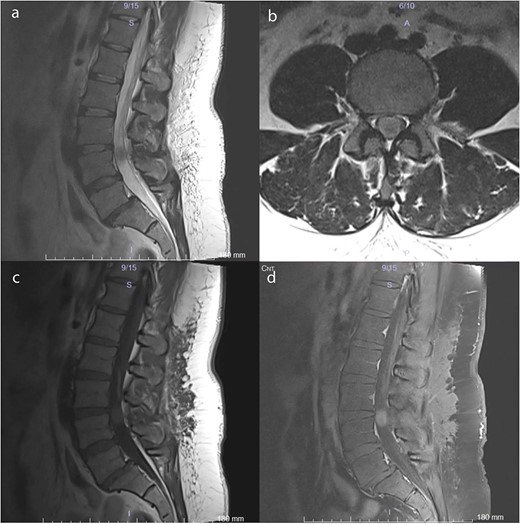

A 38-year-old female with a 1-month history of tailbone pain was admitted to the hospital. No significant medical history was present. On examination, all lower extremities were rated 5/5 for motor function. The senses and reflexes were symmetrical and intact. The patient did not report any problems with urinary or fecal continence. MRI revealed an intradural lesion at the L4 level (Fig. 1).

Preoperative MRI scans demonstrate a 17 × 12 × 15 mm intradural lesion posterior to the L3–4 disc and upper part of the L4 corpus. (a) The edge of the hypointense lesion is not so sharp in the midsagittal T2-weighted image. (b) In contrast to the sagittal T2-weighted image, the tumor appears to be hyperintense in the axial T2-weighted image. Because the nerve fibers are compressed by the tumor toward the dura CSF is not visible. (c) Midsagittal T1-weighted image shows a barely noticeable intradural tumor that is isointense with the vertebral body. (d) On midsagittal contrast-enhanced T1-weighted image, the tumor was homogeneously enhanced and became prominent.